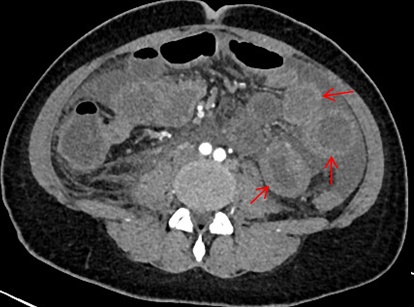

办好住院已经是1月13日下午四点了,介入科方淳主任及团队加班加点,当天晚上就为患者做了肠系膜动脉和静脉造影,结果没有发现大血管的问题,但是小血管充血、丰富,呈梳子样改变(称为“梳子征”,图1)。排除了肠系膜大血管的问题之后,高度怀疑肠系膜小血管炎可能,事不宜迟,赵家胜主任通过电话联系到风湿免疫科值夜班的王璇主治医生,王医生仔细询问了病史,了解到患者有过脱发和自发性流产的病史,结合本次肠道小血管炎的表现,高度怀疑系统性红斑狼疮引起的肠系膜血管炎。为了缓解患者的腹痛,挽救病人的生命,王璇医生基于对病情的判断,在化验结果尚未出来的情况下果断使用了糖皮质激素,第二天早上(1月14日)患者腹痛和恶心、呕吐即明显好转,患者胃口也开了,随后吃了点半流质,但下午又出现了腹痛和呕吐,这时化验结果也出来了(见图2),狼疮的标志性抗体-抗Sm抗体和ds-DNA抗体均阳性,证实了系统性红斑狼疮的诊断。赵主任和风湿免疫科汤建平主任共同查房后认为系统性红斑狼疮诊断明确,以急性腹痛起病,而且一发病就表现为狼疮危象的红斑狼疮少见,常规剂量激素疗效不佳,腹部CT结果显示肠壁水肿和胸腹水有进展(见图3、图4),需要立即进行大剂量激素冲击治疗。

图3. 1月15日CT肠壁增厚水肿(箭头所指)